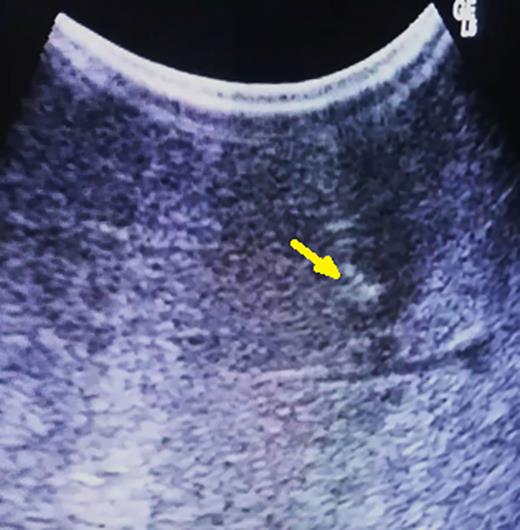

During the transection, close to the depth previously defined, intraoperative ultrasonography is repeated, and a well-defined area containing the tumor and methylene blue will be identifiable, despite the disruption of the hepatic parenchyma (Fig. 3). Resection is completed and specimen checked to confirm the presence of the lesion inside.

After parenchymal disruption, hyper-echoic lesion still clearly by ultrasonography (arrow).